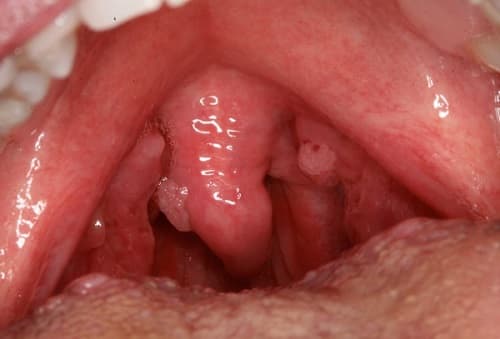

- Ban đầu, bạn sẽ thấy các nốt u nhú có kích thước nhỏ li ti, có màu hồng, nhô cao. Những tổn thương này thường không gây đau hoặc ngứa. Tuy nhiên, chúng có lớp niêm mạc mỏng nên rất dễ tổn thương và chảy máu trước những tác động ngoại lực. Đôi khi, sùi mào gà miệng cũng có thể xác định dưới dạng những nốt sùi có hình đĩa bẹt, hình tròn nhỏ, màu hồng và bề mặt khá thô ráp.

- Sau một thời gian, nếu không điều trị, các nốt sùi mào gà sẽ nhanh chóng phát triển thành các mảng rộng. Quan sát sẽ thấy chúng khá giống súp lơ hoặc mào gà. Những nốt sùi này thường có bề mặt mềm, khi dùng tay ấn sẽ thấy chúng tiết ra dịch mủ.

Hình ảnh bệnh sùi mào gà ở miệng